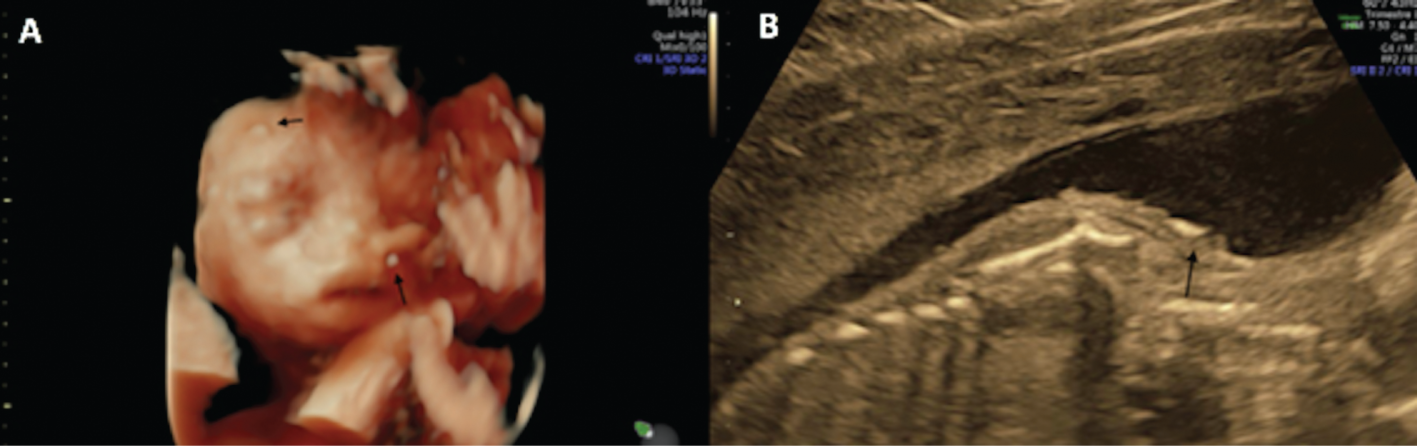

After a normal first trimester ultrasound, a 20-year-old primigravida woman was diagnosed at 27 weeks of gestational age (GA) with fetal growth restriction (FGR). The estimated fetal weight was at the 0.7th percentile. The fetus had facial dysmorphism with the mouth constantly open as an eclabium, hypoplastic nose (Figure 1), intragastric hyperechoic content (Figure 2) and skin scaling with skin particles floating in the amniotic liquid (Figure 3). The amniotic liquid was slightly hyperechoic with sedimentation of skin scales observed by vaginal ultrasound (Figure 4). No visceral abnormality was found. The amniocentesis performed showed an alpha-fetoprotein increased ten-fold (60,500 μg/L). Those findings recall a severe congenital ichthyosis and termination of pregnancy was proposed, but refused. Within several weeks we observed progressively fetal immobilism and hydramnios. At 30 weeks of GA corticosteroids prophylaxis and tocolytics were administrated to prevent premature delivery secondary to uterine contractions due to hydramnios. At 31 weeks of GA the patient gave birth to a baby boy of 1380 g, 40 cm of height and 28 cm of cranial circumference and normal cord blood pH. The Apgar score was 3–3–3. The baby boy had severe ichthyosis, atrophic ears, everted eyelids (ectropion), a hypoplastic nose, eclabium and stiffened skin surface. The couple opted for palliative care and the baby died at 33 min of life. An autopsy was refused. Comparative genomic hybridisation (CGH) array and clinical exome on cord blood were negative.

Skin scaling on 3D reconstruction of the face and on the shoulder.

Black arrows on Figure (A) and (B).

Some authors [3], [4], [5], [6] used three-dimensional (3D) and four-dimensional (4D) analysis to better visualise the facial dysmorphism. These are diagnostic tools that we recommend using as they helped us to confirm our suspicion, and the parents to better understand the pathology.